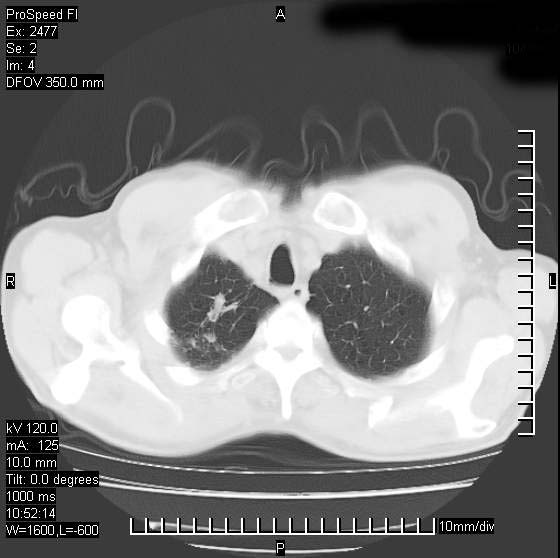

以下是引用天南地北在2007-10-9 14:29:00的发言:[br]1:右上肺结核[br]2:右肺下叶肿块:不支持肺癌,首先考虑炎性病变-肺脓疡可能性大[br]理由:1:临床病史支持,肺脓肿症状不明显应该是不规则服药造成。[br] 2:肿块边缘模糊,周围可见炎性渗出,长毛刺,内见支气管征,不过有点不规则。[br] 我感觉下肺癌这个诊断有点偏左,建议积极抗炎治疗后复查

以下是引用卜一在2007-10-9 15:55:00的发言:[br][br] [br] 1:右上肺结核[br]2:右肺下叶肿块:不支持肺癌,首先考虑炎性病变-肺脓疡可能性大[br]理由:1:临床病史支持,肺脓肿症状不明显应该是不规则服药造成。[br] 2:肿块边缘模糊,周围可见炎性渗出,长毛刺,内见空气支气管征,不过有点不规则。[br] 我感觉下肺癌这个诊断有点偏左,建议积极抗炎治疗后复查![br]支持! [br] [br] [br]

以下是引用wxy7406在2007-10-9 21:02:00的发言:[br]结合临床病史首先考虑感染性病变,但周围型肺癌不能除外,1.患者年龄偏大2.临床有咯血3.(也觉得是最重要的一点)病灶内有偏心性空洞。

以下是引用王仕学在2007-10-9 13:48:00的发言:[br]右下肺周围性肺癌可能性大,最好活检吧

以下是引用hhcckk在2007-10-9 15:18:00的发言:[br]右上肺病灶考虑结核,病灶多种形态并存(纤维化、增殖性病灶并存)[br]右下肺病灶比较难说,个人意见更趋向于“天南地北”的诊断----肺脓肿[br]1、病人有明显的寒战,高热,肿瘤病人很少出现[br]2、病灶周围的肺纹理走向柔和,没有肿瘤病灶常见的集束征[br]3、病灶边缘的毛刺较长,恶性肿瘤多为短毛刺[br]痰中血丝和病人的年龄是两个不利于良性肿块的因素,建议早点活检

以下是引用ydx_74在2007-10-9 15:53:00的发言:[br]右上肺结核,右下中心性肺癌可能大,肺门淋巴结肿大。